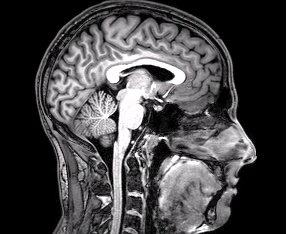

The cerebral cortex – our wrinkled outer layer – handles language, planning, and perception, with lobes that specialize but rarely work alone. Beneath it, the thalamus relays sensory traffic, while the basal ganglia choreograph movement and habits. The limbic system, including the hippocampus and amygdala, stitches context to emotion, deciding what gets remembered and what can be safely ignored.

Farther down, the brainstem regulates heartbeat, breathing, and wakefulness, the nonnegotiable basics of being alive. Tucked under the back, the compact cerebellum fine‑tunes motion and timing and may even assist with certain thinking tasks. White matter tracts, sheathed in myelin, bind this landscape into a high‑speed network, and ventricles circulate cerebrospinal fluid that cushions, nourishes, and cleans.